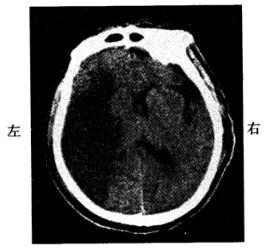

问题 男,60岁。早晨睡醒后左侧肢体无力,刷牙时无法拿杯子。有糖尿病和高血压病史,无心脏病史。半天后到急诊就诊。查体:左侧肢体肌力3级,腱反射高于右侧,左侧Babinski征阳性。左侧肢体痛温觉减退。脑CT见图示:

解析 本题考查的目的是综合临床资料和CT图像作出脑血管病的诊断。从上题的脑缺血性卒中与出血性卒中的鉴别要点表中很容易得出标准答案为D。短暂性脑缺血发作的体征一般1~2小时恢复,而且以单肢瘫等局限体征为多见,CT上一般没有梗死灶。脑栓塞一般在活动状态下,数秒钟即出现明显的大脑症状,大多数患者有心房颤动等栓塞灶的来源。这些均与本例不符合,故为缺血性卒中,以脑血栓形成为正确答案。